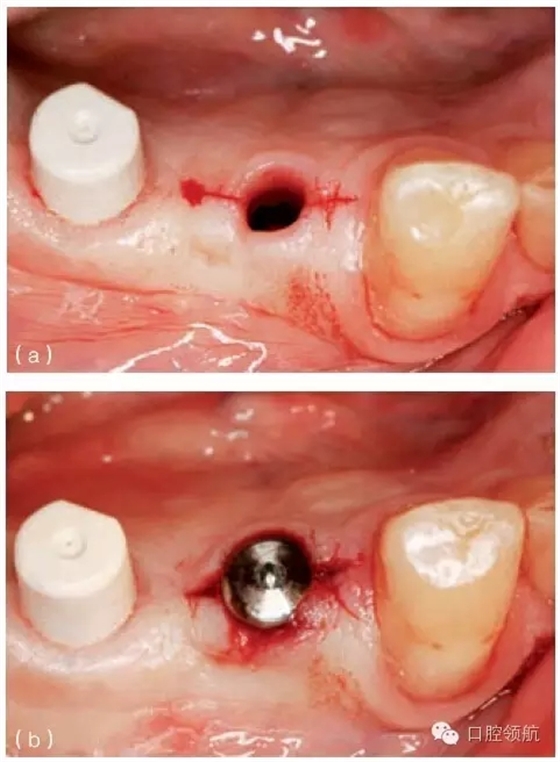

另外一個方面,深的袖口將妨礙修復(fù)體完全就位(圖9.26)。通常可以通過放射學(xué)檢查,確認(rèn)修復(fù)部件的就位情況,包括種植體與基臺的連接部分。即使是內(nèi)連接,轉(zhuǎn)移體或者其他修復(fù)部件也會因深袖口而不能就位。以下技術(shù)可以用于解決這些問題:可以在局部麻醉下,插入喇叭狀或者外展的基臺,以非手術(shù)的方式擴大袖口(圖9.27 a,b),然后再通過放射學(xué)檢查確定部件的完全就位。組織會受壓發(fā)白,15分鐘后,軟組織將會擴張,以允許理想修復(fù)部件的就位,這樣治療將得以繼續(xù)。有時,需要在鄰面做兩個小切口,以緩解袖口軟組織張力(圖9.28 a,b)。通常不需要縫合。一旦袖口組織塑形完成,可運用最佳塑形的臨時(圖9.29)或最終部件(圖9.30),來維持理想的軟組織外形。

圖9.27 (a)種植體植入時,使用窄頸的愈合基臺。(b)二期暴露時,可以采用寬頸愈合基臺,拓展袖口以適應(yīng)修復(fù)的需要。

圖9.28 (a)做鄰面切口,使軟組織易于擴張,以適應(yīng)外展的愈合基臺。(b)寬頸愈合帽就位,阻力很小。